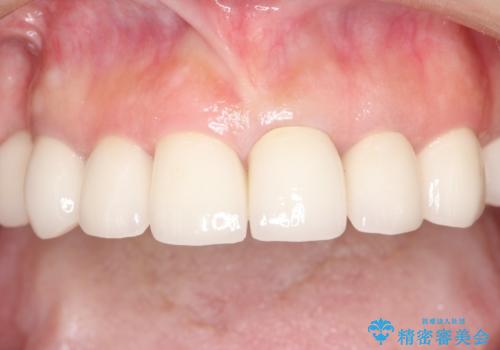

セラミックと矯正を併用してきれいな前歯へ

③セラミック装着

今回矯正治療で歯並びを整えた後に、セラミックを装着することにより、審美的・機能的に優れた仕上がりにすることができました。